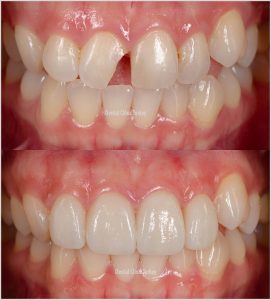

Le sourire esthétique que nous appelons Hollywood Smile peut être appliqué à presque toutes les personnes (de plus de 18 ans). Seul le mode d’application peut changer. Chez certaines personnes appliquées, l’application peut être faite sans ou très peu de taillage de la dent. Cette application peut généralement être des facettes.

Que faut-il faire pour un beau sourire était notre première question. Qu’est-ce qui suit, faut-il intervenir sur les dents ? Cette opération n’est pas toujours requise. L’esthétique d’un sourire peut être obtenue en quelques étapes simples. Les techniques de blanchiment des dents peuvent en faire partie. Le type de revêtement le plus couramment utilisé dans le traitement esthétique est la facette qui est appliqué uniquement sur la surface visible des dents.